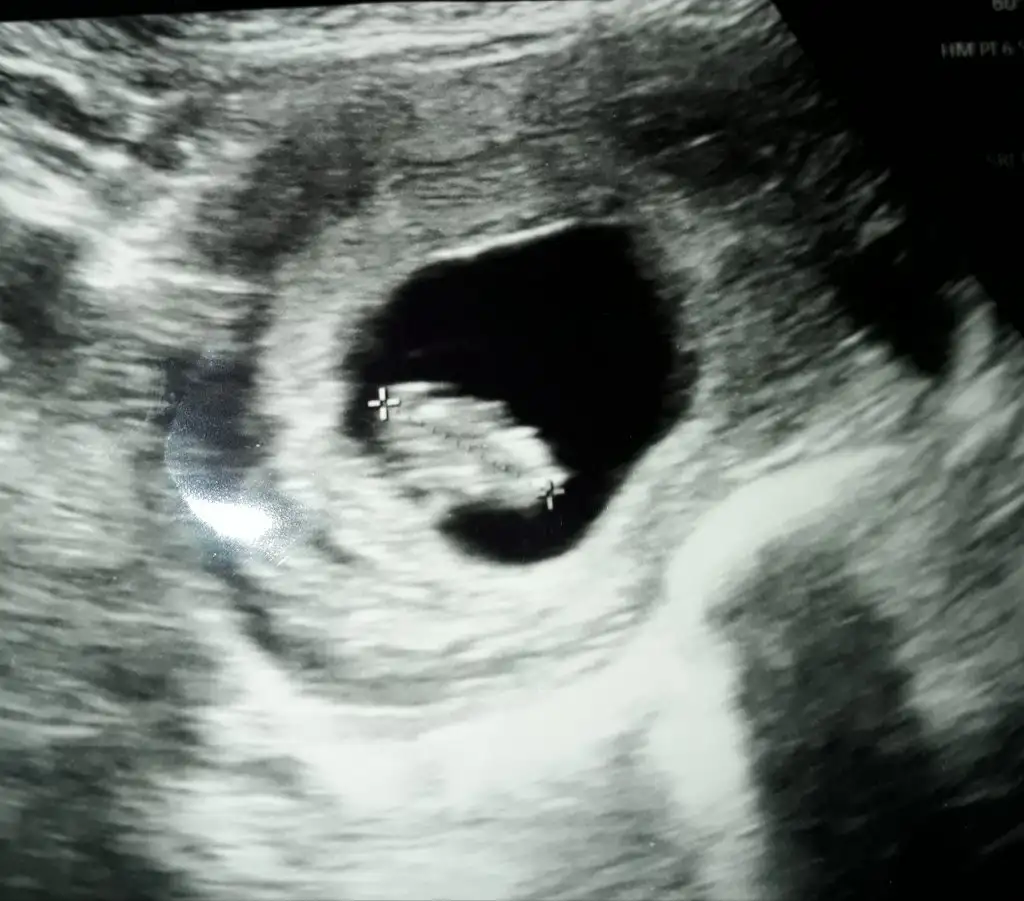

Buna göre erkek dedi herkes. Sizin tahmininiz farklı bisey heralde.Ramzi teorisine göre ( bilimsel bir araştırma sonucuymuş ve %85 doğruluğu varmış). İlk 6-8 haftalık ultrason görüntüsüne göre bebeğin kesenin içersinde soldan ya da sağdan girişine göre cinsiyet tahmini yapılıyor. Bilimsel olunca tecrübeli annelerimiz yada anne adaylarımızdan yardım istiyoruz. Doğruluğu var mı öğrenmek adına :) Bizleri aydınlatırsanız çok seviniriz. bu teorieye göre;

Vajinal muayeneyle bakıldıysa eğer;

Sağdan girmiş gözüküyosa aslında solmuş ve ERKEK,

Soldan girmiş gözüküyosa aslında sağmış ve KIZ ,

Karından bakıldıysa eğer,

Soldan girmiş gözüküyosa gerçektede solmuş ve ERKEK,

Sağdan girmiş gözüküyosa gerçekte de sağmış ve KIZ,

Buna göre erkek tabiki en iyi 11 12 13 haftalar olmalıEki Görüntüle 2682785

Ikra meyra bu kuzenimin 6+5gunluk usg si karından.Keseye göre merak ettik.Bi bakarmisin rica etsem.